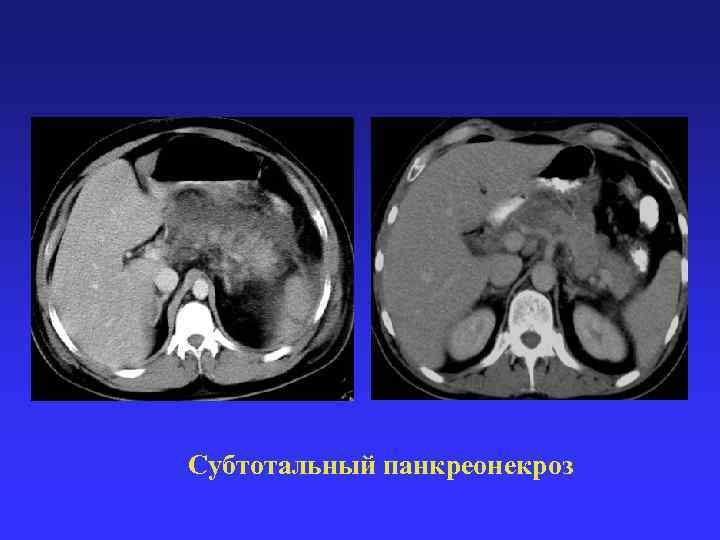

Субтотальный панкреонекроз Субтотальный панкреонекроз